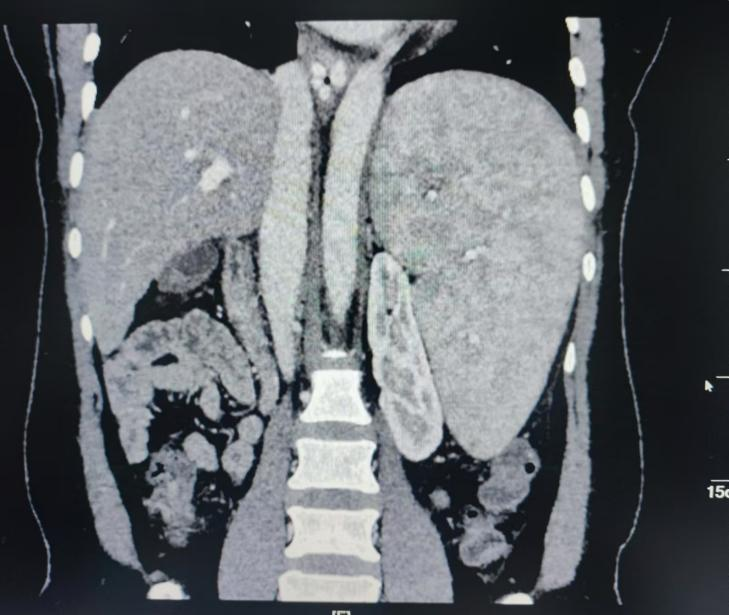

术前CT检查

患者蒋女士今年50岁,从2018年至今已经有五次食管胃底静脉破裂出血病史,做3次胃底静脉硬化治疗。半月前胃底再次出血,入住自治区南溪山医院消化内科。经评估病情后考虑患者乙肝后肝硬化巨脾脾功能亢进,白细胞、红细胞、血小板“三系”减低,多次硬化剂治疗再次出血,有手术指征,经肝胆胰脾外科会诊后拟全麻下行全麻行腹腔镜下脾切除术+贲门血管离断术。